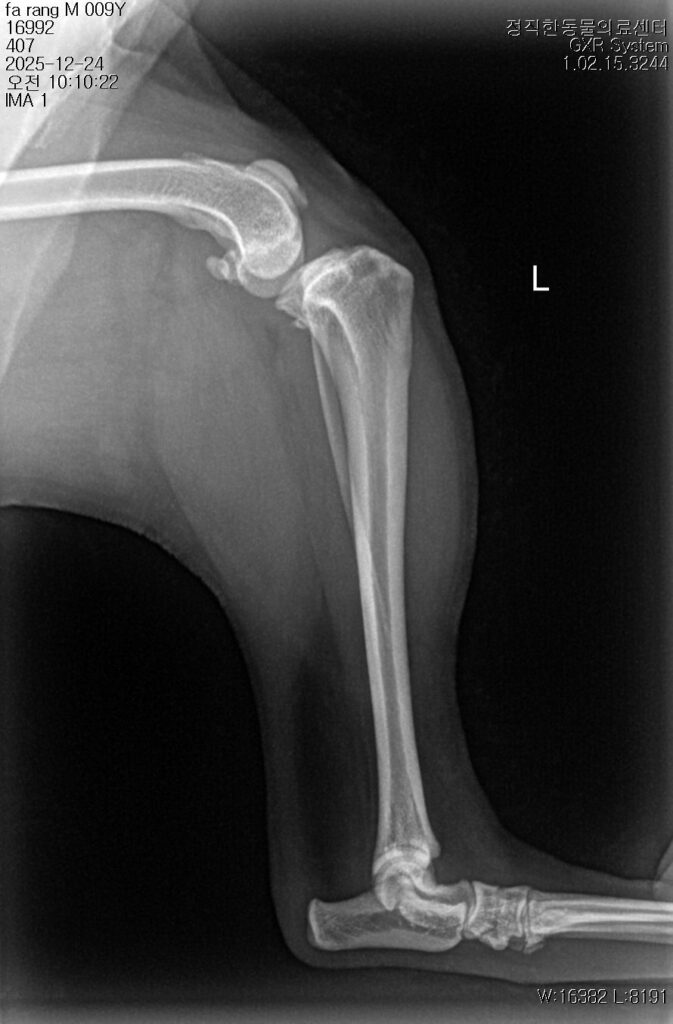

수술 전

(Before)

수술 후

(Afrer)